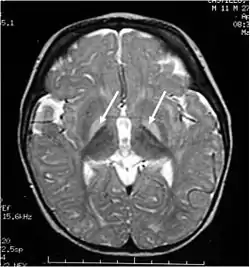

اليرقان النووي (بالإنجليزية: Kernicterus) هو تلف دماغي ناجم عن البيليروبين. البيليروبين هو عبارة عن مادة شديدة السمية للأعصاب عندما ترتفع نسبتها في الدم، وهذه الحالة تعرف بفرط بيليروبين الدم. إن فرط بيليروبين الدم قد يُسبب انتقال وتراكم البليروبين في القشرة الرمادية المكونة للنظام العصبي المركزي، وهذا قد يؤدي إلى ضرر عصبي لا رجعة فيه. تبعاً لمستوى الإصابة، وتتراوح اعراض المرض من اعراض طفيفة وربما غير ملحوظة سريرياً إلى تلف دماغي شديد وقد يؤدي احياناً إلى الموت. الاطفال حديثي الولادة هم الأكثر عرضة للتلف العصبي الناجم عن فرط البليروبين؛ لذلك يجب مُراقبة نسبة البليروبين في الدم خلال هذه الفترة العُمرية بحذر.